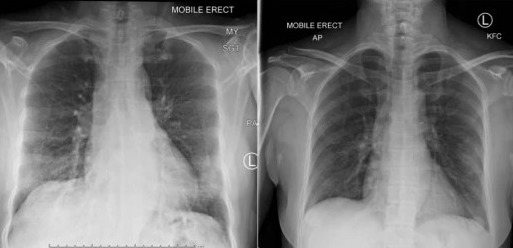

radiografia mostra a recuperação dos pulmões da paciente

O caso estudado foi de uma chinesa de Wuhan, que viajou para a Austrália 11 dias antes de procurar o departamento de emergência em Melbourne, com quadro leve a moderado de covid-19. A paciente, de 47 anos, apresentou sintomas por quatro dias: letargia, dor de garganta, tosse seca, dor no peito, falta de ar e febre subjetiva. Não tinha maiores complicações prévias de saúde, não fuma, não esteve no mercado de Huanan – origem do vírus –, nem teve contato com outros casos conhecidos de covid-19. Depois de 12 dias internada, foi liberada para permanecer isolada em casa (ou onde estivesse hospedada) e, após mais dois dias, deixou de apresentar sintomas.